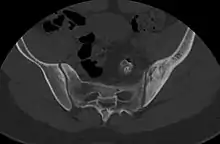

- ↑ Nguyen, Nghi; Khan, Mujahid; Shah, Muhammad (2017). "Primary B-cell lymphoma of the pelvic bone in a young patient: Imaging features of a rare case". Cancer Research Frontiers. 3 (1): 51–55. doi:10.17980/2017.51. ISSN 2328-5249.